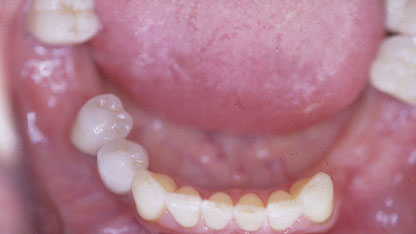

Vues en bouche au maxillaire inférieur

Le stellite est confectionné avec un alliage à base de cobalt, biocompatible, ayant une bonne résistance à la corrosion. Il est plus léger que l'appareil en résine

Il s’intègre parfaitement et présente une grande stabilité. Dans certains cas, des attachements de précision non visibles(boutons pressions, taquets, glissières) peuvent remplacer des crochets inesthétiques